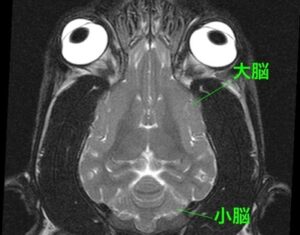

・脳に発作を起こすような異常は見られず

・脳脊髄液(脳や神経のまわりを流れる液)

の異常も認められない

<MRIって?>

MRIは磁気共鳴画像診断とも呼び、強力な磁力と電波により臓器や血管などを画像化する検査